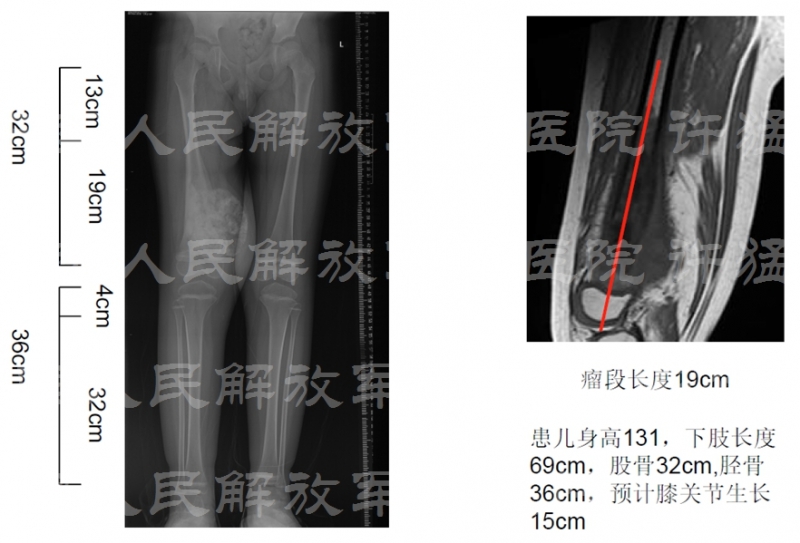

患者男性,6岁,主因“右大腿下段疼痛,肿胀2月余”入院。查体:右大腿下段疼痛,内侧为主,皮温高,静脉怒张,压痛,皮肤活动度差,肢体远端感觉可,可扪及足背动脉。

核磁显示股四头肌伸膝装置受到肿瘤累及

患者男性,9岁,身高1.2m,右大腿肿胀疼痛1个月。

治疗前相关检查:

核磁显示穿刺通道有污染伸膝装置的可能